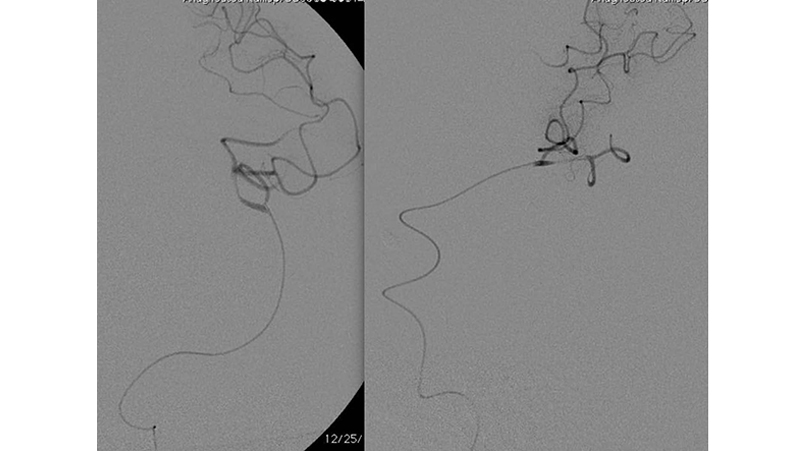

Εικόνα 5: Έκπτυξη stent retriever κατά μήκος του αποφράσσοντος θρόμβου.

Εικόνα 6, 7: πλήρης αποκατάσταση της ροής και επανακαναλοποίηση της μέσης εγκεφαλικής αρτηρίας μέσα σε 20 λεπτά, χωρίς κλινικές επιπτώσεις.